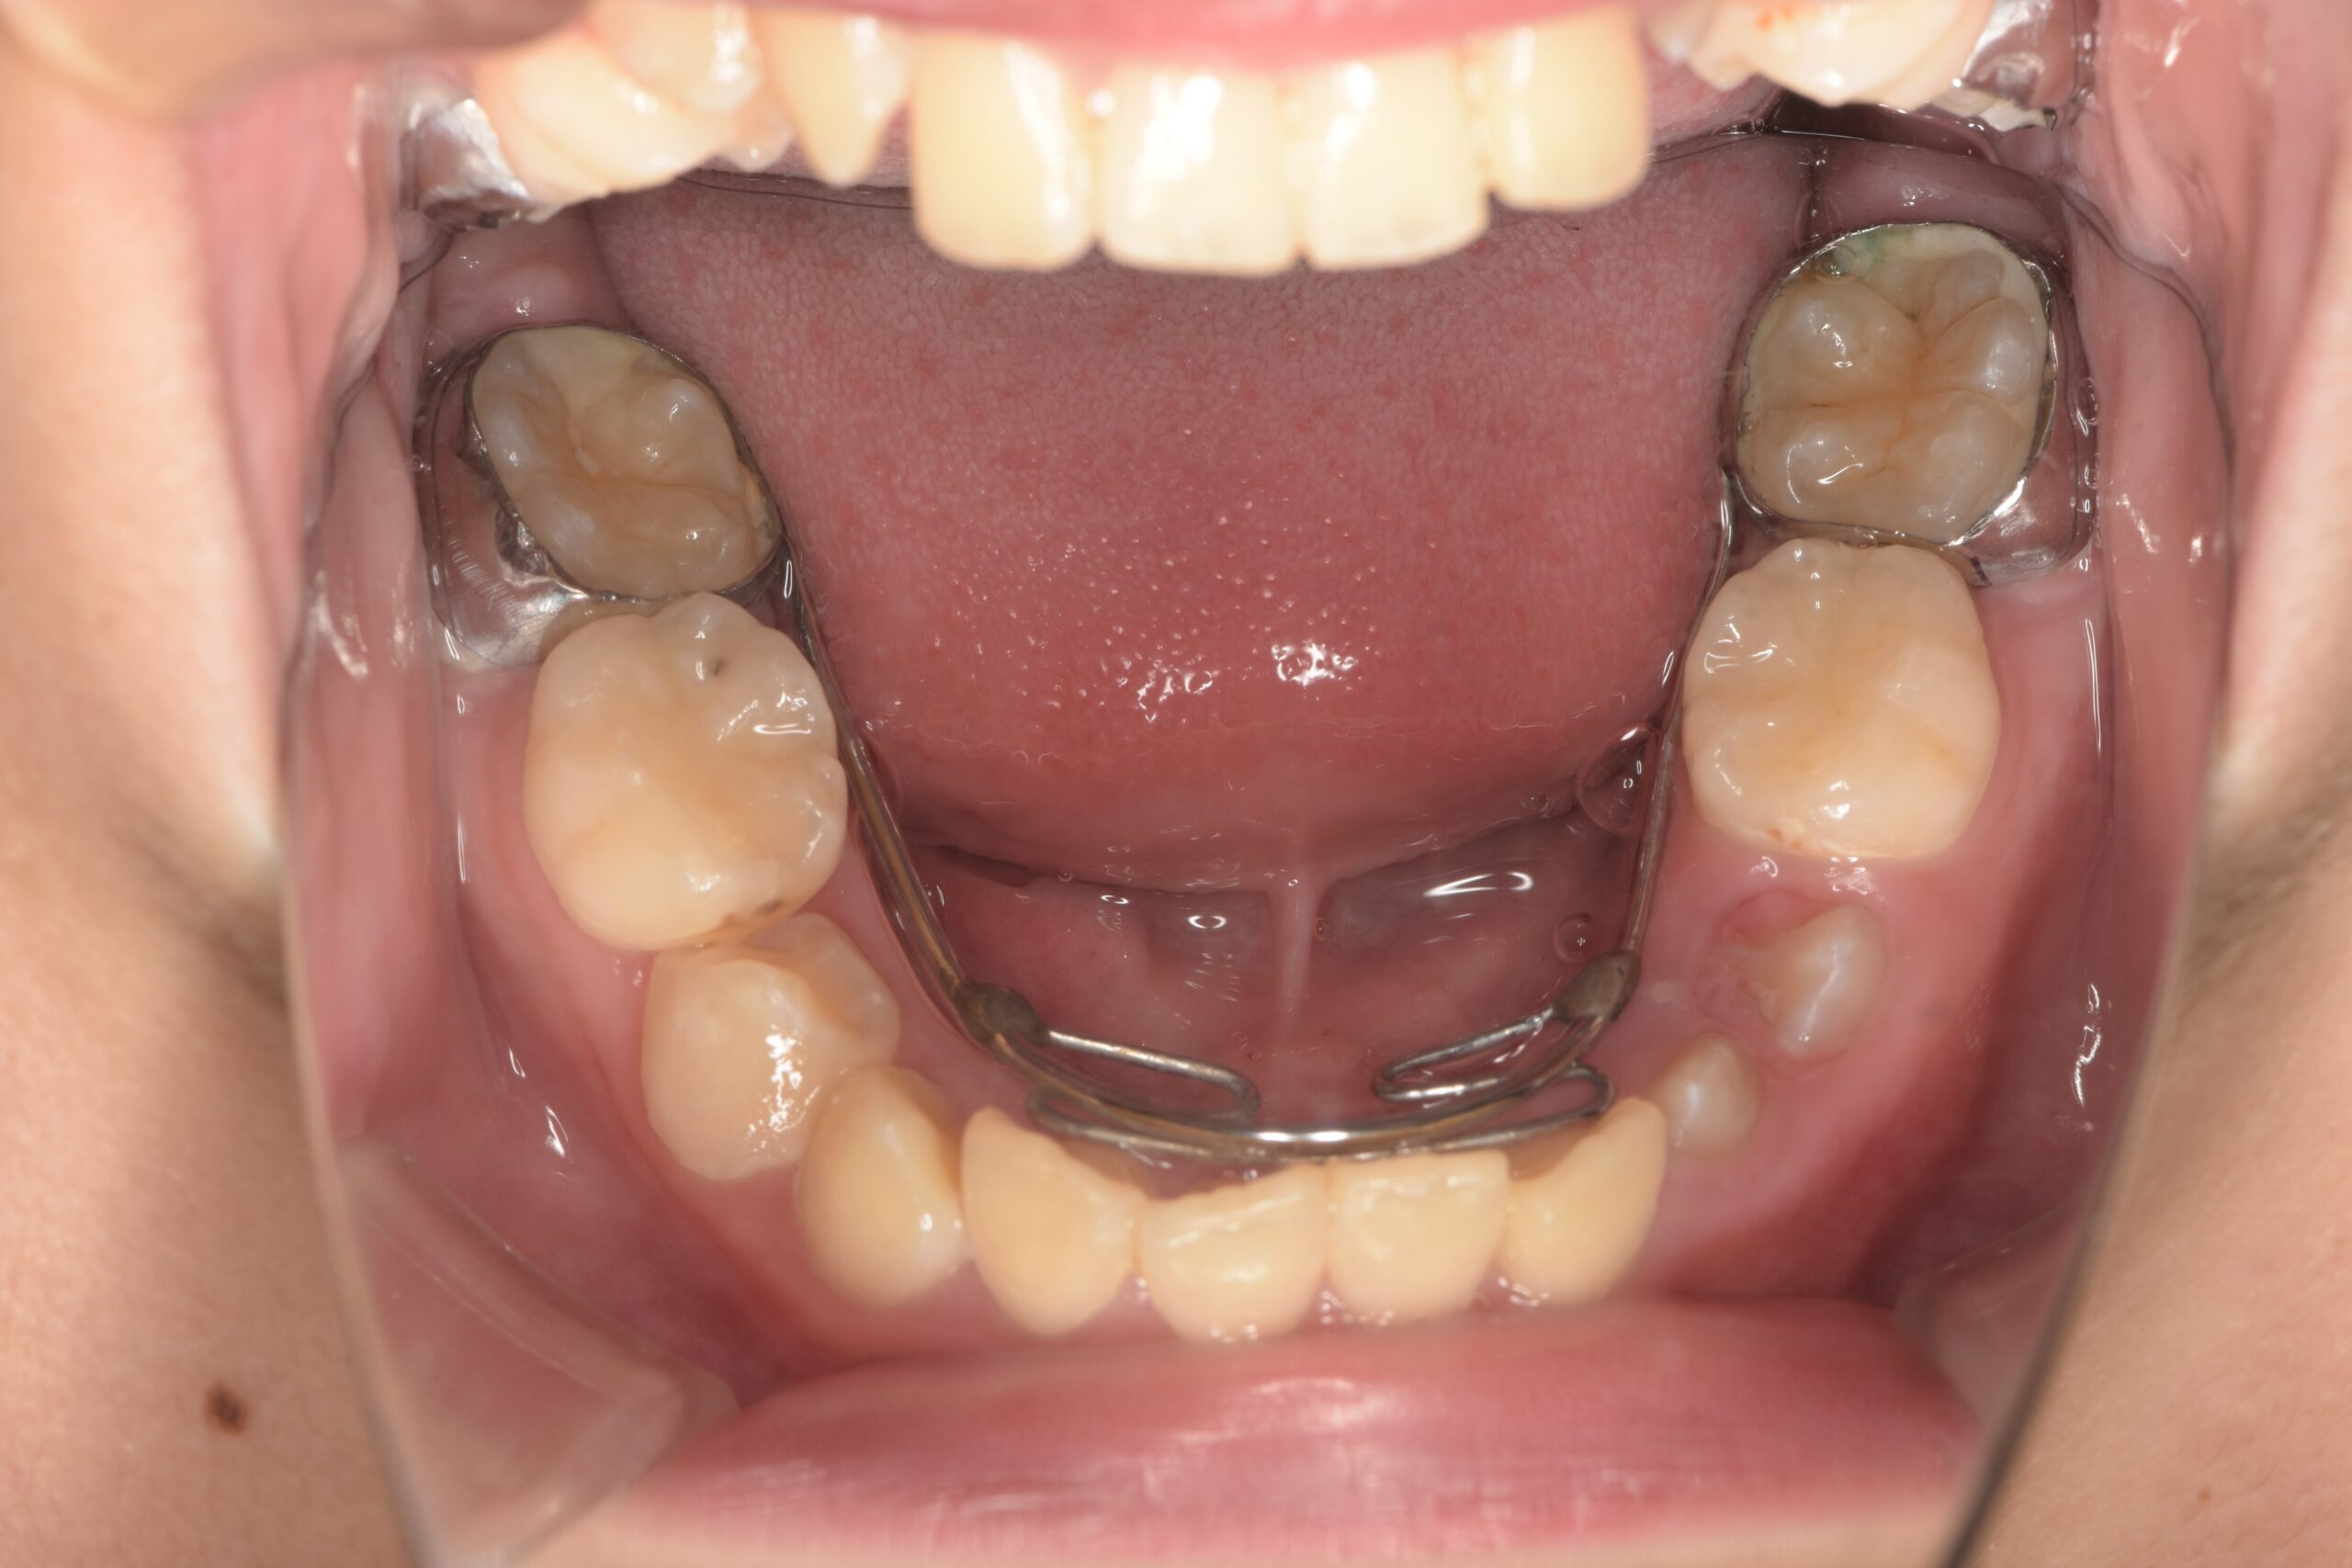

第一大臼歯が前に移動しないように装置で抑えます(上顎)

同じく装置で抑えます(下顎)